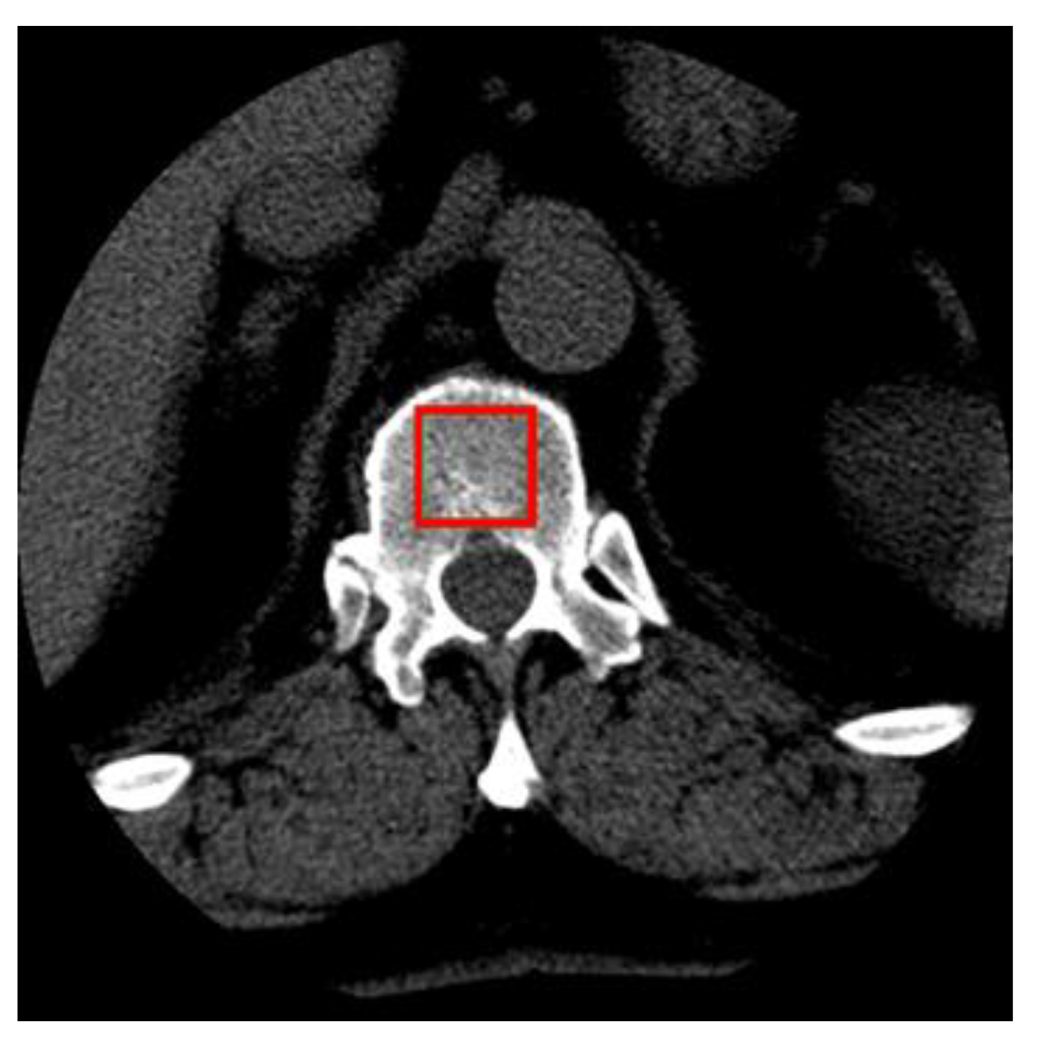

2.1. Material